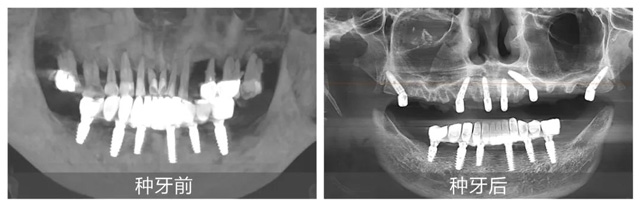

在配備數字化導板系統的現代化手術室里,黃杰終于迎來期盼已久的“試煉場”。短短一年,就已經成功種植修復2100+顆牙,完成無牙頜即刻負重手術110臺。不僅在種牙數量上取得了突破,在質量方面也同樣出色。

日前,黃杰為一位種牙顧客實施“即拔即種”手術,從拔除殘根到植入種植體僅用15分鐘,創面控制得如同經過精密計算一般。但讓他最有成就感的,還是那些從牙槽外科延續而來的“全流程治療”:曾有位患者因埋伏多生牙導致囊腫,他先微創拔除患牙,待運用頜面外科的骨移植修復骨缺損后又為其完成種植修復。“能看到顧客從治療到重獲咀嚼功能的完整過程,這是口腔醫生特有的幸福。”